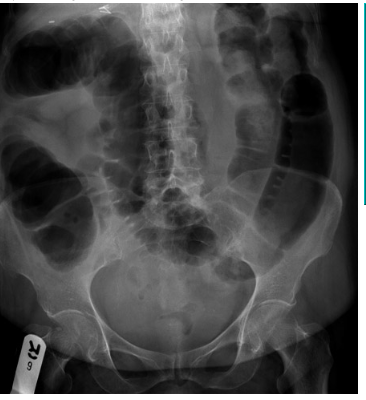

24-year-old patient with suspected appendicitis. What does the image show?

Small bowel obstruction

Dilated loops of bowel with valvulae conniventes – lines crossing the full width of the bowel – indicates small bowel obstruction.